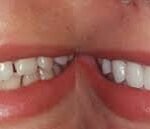

Affordable All-on-4 Dental Implants in Brisbane: Your Comprehensive Guide

Introduction: Are you considering All-on-4 dental implants but worried about the cost? Sandgate Bayside Dental is here to make this transformative procedure accessible to...